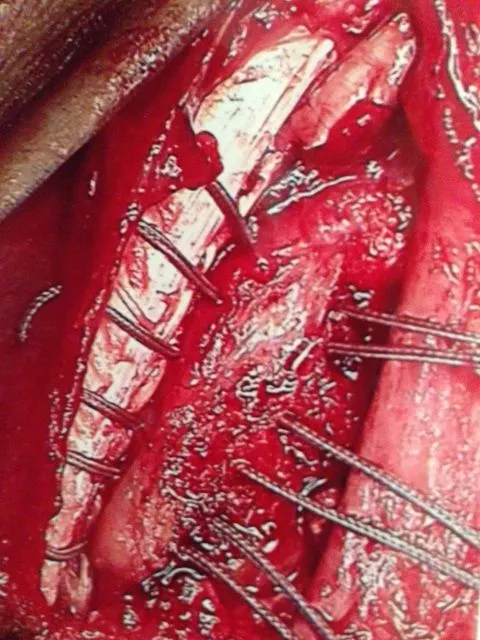

Peroneus Brevis Split Tear with Surgical Repair and Removal of Torn Tendon Portion. (below)

Partial Tear Peroneus Brevis Tendon. (below)

Removal of Torn portion and debulking of tendon. (below)

Final Placement of Peroneal Tendons back in the fibular groove and suture replacement for repair of Superior Peroneal Retinaculum and Tendon Sheath. (below)